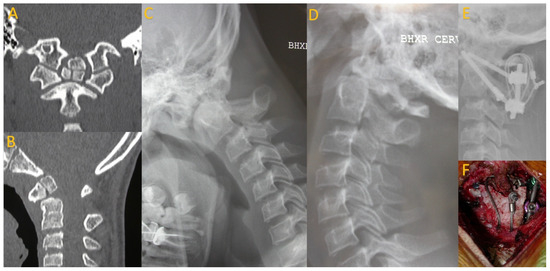

Figure 2.

A 16-year-old boxer who presented after developing transient paraplegia while boxing. CT imaging revealed os odontoideum (A,B) with hypermobility on flexion and extension cervical X-rays (C,D). He underwent posterior C1–2 fusion with instrumentation, wiring, and allograft (E,F).